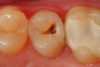

A 66 year-old female patientpresented with a "stained" occlusal groove in tooth No. 13 that did not "stick" with an explorer tip (Figure 1).  Upon radiographic examination (Figure 2), a rather large carious lesion was discovered that encroached upon the dental pulp.  There were no other clinical or subjective signs to alert the clinician or patient to the extent of the damage that had already occurred in the tooth. Figure 3 through Figure 5 show selective caries removal using a round end plastic polymer bur (SmartBurII, SS White).  Before caries removal, isolation of the operative quadrant was achieved using Isovac (Zyris). Because of its Knoop hardness of 90, SmartBurII allows for removal of infected dentin only, while allowing affected dentin to remain for potential remineralization with a bioactive liner or base material.

Fig 3	After a fissurotomy bur is used to conservatively open into the groove, a rather extensive carious area is discovered.

Figure 3